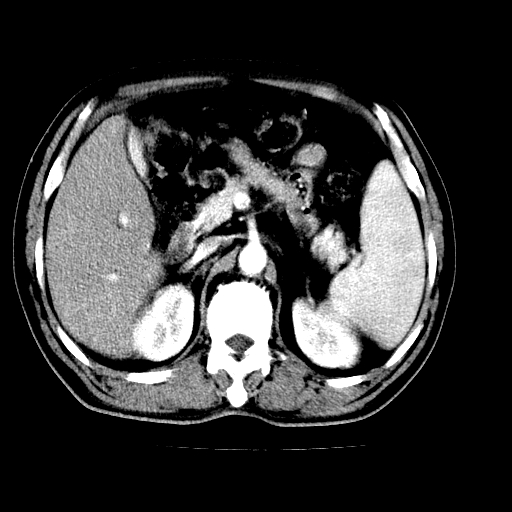

肝左叶不规则软组织肿块影,边缘不规整邻近肝实质受累分界不清;肝内胆管(左叶)明显扩张成“软藤状”,诊断:肝左叶胆管细胞癌。

左叶胆管细胞癌累及胆总管,门脉左支受侵,慢性胆囊炎胆结石,左肾小囊肿

肝左叶不规则软组织肿块影,边缘不规整邻近肝实质受累分界不清;肝内胆管(左叶)明显扩张成“软藤状”,诊断:肝左叶胆管细胞癌。胆囊钙乳症。

支持 1)肝左叶胆管细胞癌伴胆总管及门脉左支受侵。2)胆囊钙乳症。